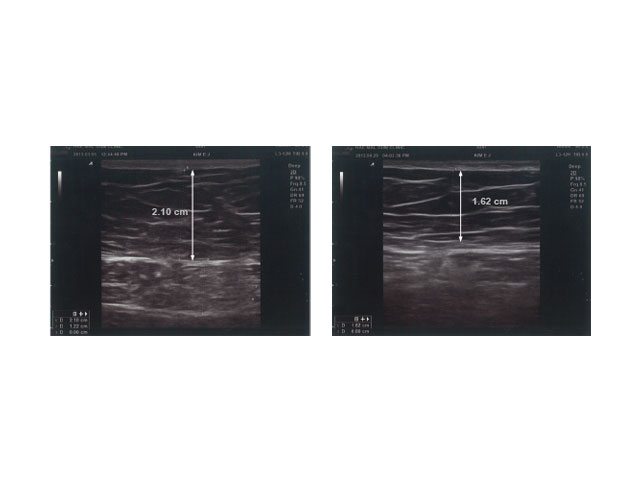

ANTES Y DESPUÉS

Con COOLshaping obtendrás los mejores resultados en tratamientos reductivos.

• Abdomen

Observaciones: Resultados 8 semanas después del primer tratamiento